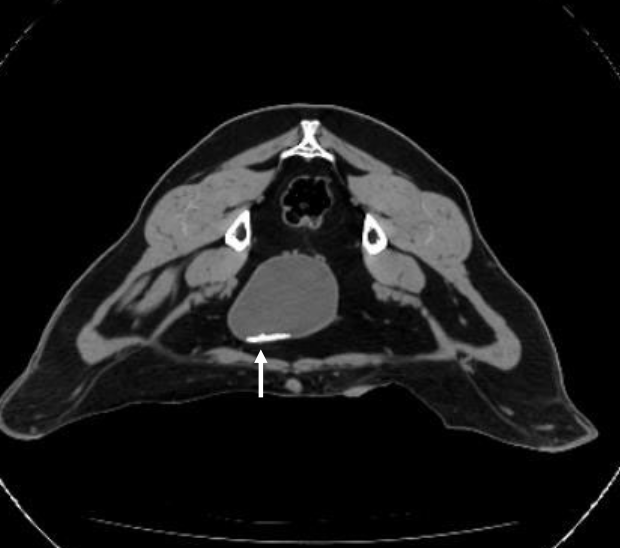

how can CT be used to identify urinary disorders in ruminants?

picks up stones, umbilical issues in calves/small ruminants (usually not cost effective)

CT scan of goat with Ca-carbonate stones in bladder